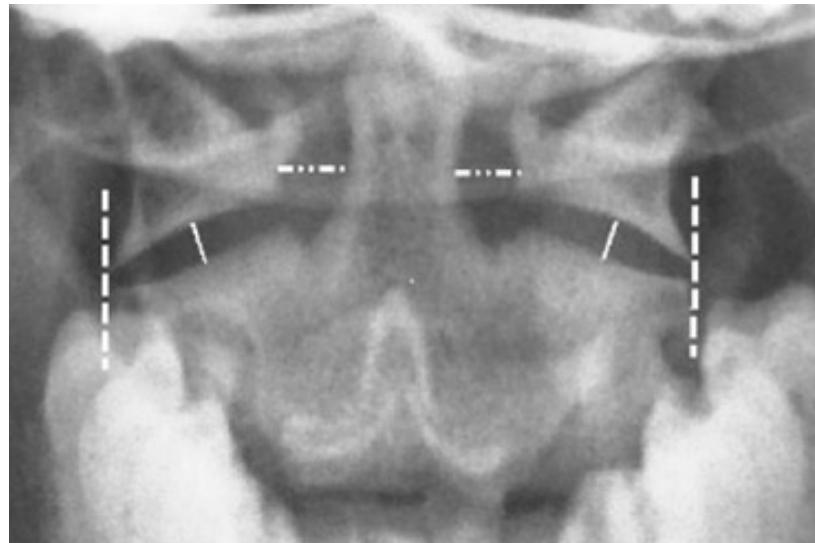

Open-mouth View:

- For C1 and C2 assessment

- Odontoid fractures

- Lateral mass fractures

- Look for: Symmetry and Continuity of bone